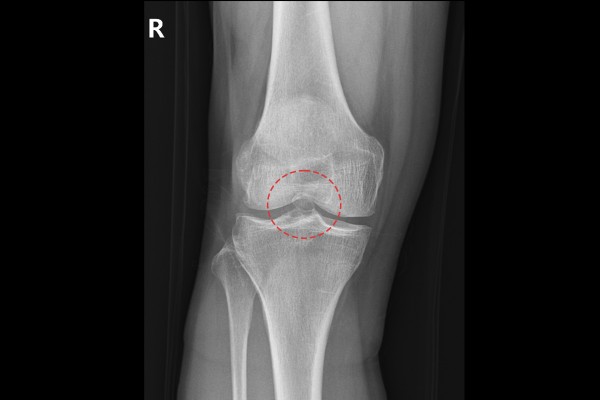

환자분의 무릎 상태를 파악하기 위해 X-RAY 촬영을 진행하였고, X-RAY에서 무릎 관절 사이에 유리체(뼛조각)가 확인됩니다.

반면 반대쪽인 좌측 무릎에서는 관절 내 유리체가 확인되지 않고, 예전에 오다리 교정술을 받으신 흔적만이 보입니다.